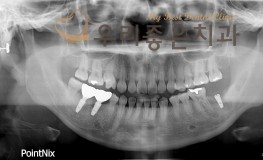

우리좋은치과 치아 상실로 인한 임플란트 보철 치료 (김** 21.05.12 ~ 21..

No.165

임플란트

2021-12-07

1574